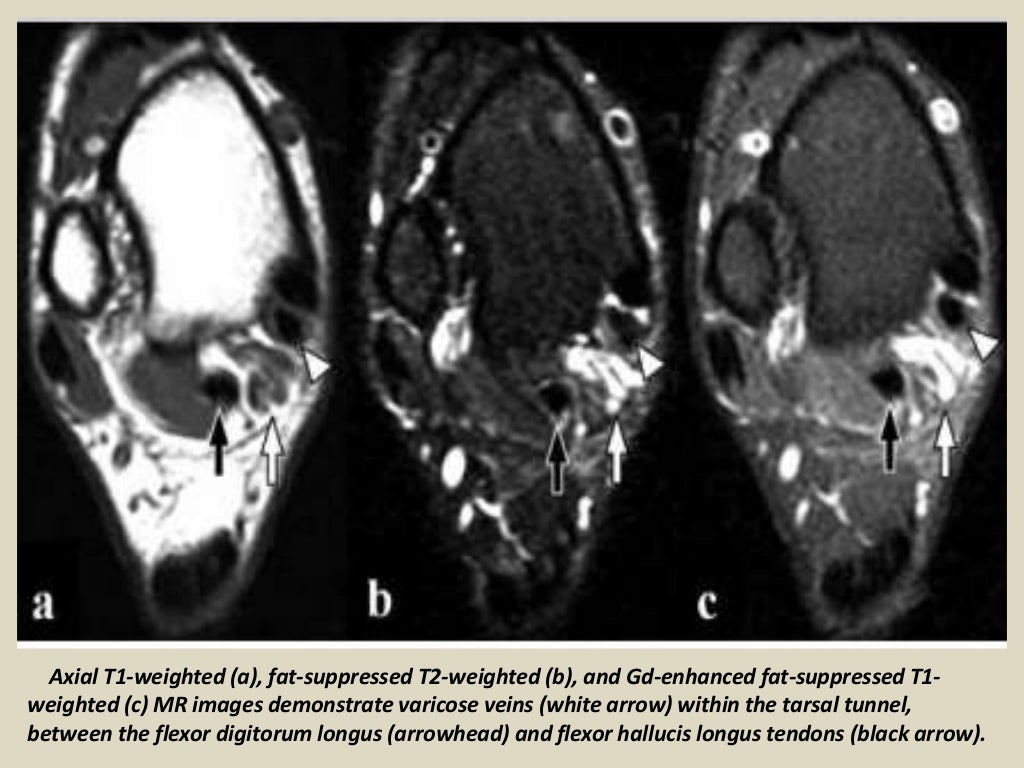

Varicose veins causing tibial nerve compression in the tarsal tunnel Tarsal Tunnel Syndrome X Ray Tarsal tunnel syndrome refers to an entrapment neuropathy (tunnel syndrome) of the (posterior) tibial nerve or of its branches within the tarsal tunnel. Mr imaging can accurately depict the contents of the tarsal tunnel and the courses of the terminal branches of the posterior tibial nerve. Tarsal tunnel syndrome is a compressive neuropathy of the tibial nerve at the level. Tarsal Tunnel Syndrome X Ray.

Tarsal Tunnel Varicosities MRI Sumer's Radiology Blog Tarsal Tunnel Syndrome X Ray Tarsal tunnel syndrome refers to an entrapment neuropathy (tunnel syndrome) of the (posterior) tibial nerve or of its branches within the tarsal tunnel. Mr imaging can accurately depict the contents of the tarsal tunnel and the courses of the terminal branches of the posterior tibial nerve. Tarsal tunnel syndrome is a compressive neuropathy of the tibial nerve at the level. Tarsal Tunnel Syndrome X Ray.